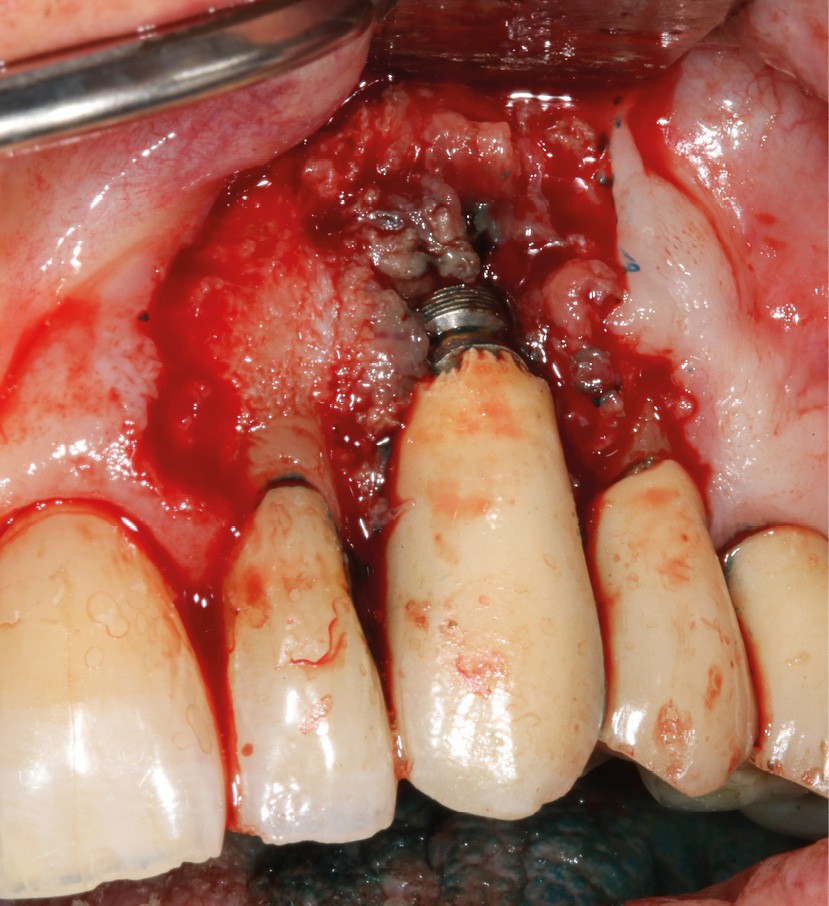

Le patient

- 70 ans

- Pas d’antécédents médicaux

- Ne fume pas

- Hygiène correcte

L’implant

- Site 23

- Mis en place il y a 12 ans

- Parmi ces longueurs d’onde, deux lasers (Er-YAG et Diode) sont intéressants dans le traitement de la péri-implantite :

– Le laser Er-YAG, utilisé pour le nettoyage, est un laser avec un milieu actif composé d’yttrium, d’aluminium et de grenat dopé à l’erbium. Avec une longueur d’onde de 2 940 nm situé dans l’infrarouge, le laser Er-YAG est un laser à haute énergie, dont la lumière est absorbée dans l’eau et dans l’hydroxyapatite et qui ne pénètre pas profondément. Ceci permet de couper des tissus mous et des tissus durs, mais également de désorganiser le biofilm bactérie.

C’est un laser idéal pour le traitement chirurgical des péri-implantites. Il permet l’élimination du tissu de granulation à la surface de l’implant et de l’os ainsi qu’une décontamination mécanique par effet photoablatif.– Le laser Diode, utilisé pour la décontamination…